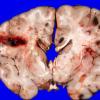

NEOPLASMS (HEMATOLYMPHOID)

Granulocytic Sarcoma (3)